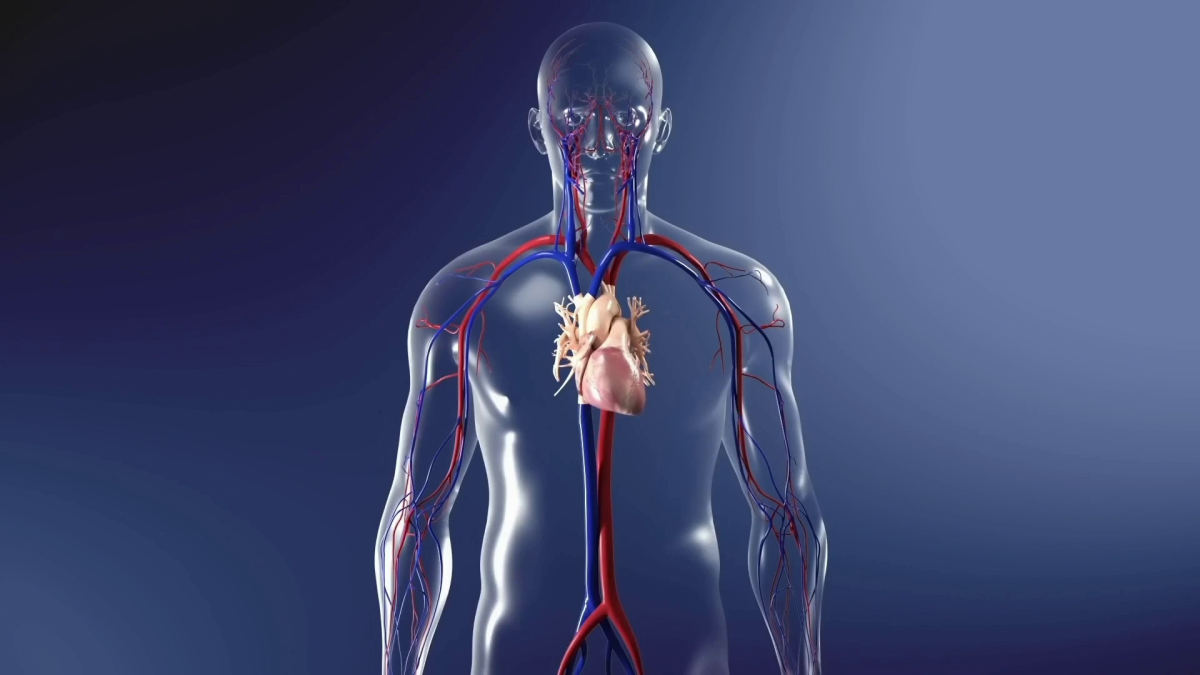

- 3D Dental Animation for procedures like cleaning, cavity filling, root canals, etc.

I have extensive experience in dental visualization and animation, ensuring that every project is accurate, professional, and visually appealing. I use advanced software to deliver high-quality videos tailored to your specific needs.

Tagged : 3d dental animation, 3d medical animation, dental models for oral health explainer, surgical animation, tray whitening